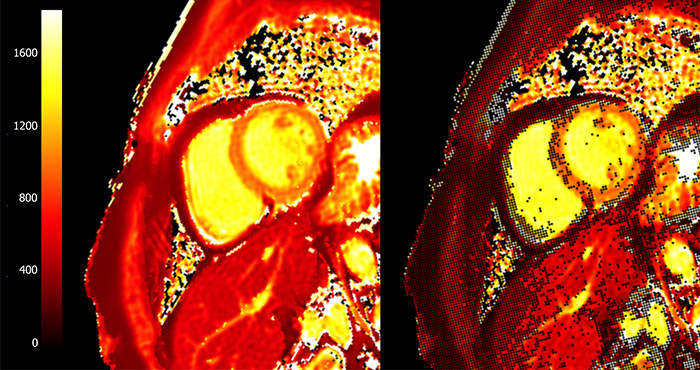

T1-картирование активно используется в диагностике инфаркта миокарда наряду с LGE. Известно, что ишемия приводит к развитию внутриклеточного отека, который, как было сказано ранее, вызывает рост времени T1 (для воды этот параметр может достигать вплоть до 5 с, в то время как типичное значение T1 в миокарде - 1-1.5 с). Инфаркт миокарда в хронической стадии (или постинфарктный кардиосклероз- ПИКС) сопровождается повышенным отложением коллагена в миокарде и образованием фиброзной рубцовой ткани, что характеризуется ростом T1.Таким образом, повышенные значения T1 (рис. 8) и ECV наблюдаются как при хронической, так и острой форме заболевания, и могут использоваться в качестве их биомаркеров. При этом рост значений более выражен при остром инфаркте миокарда, что позволяет дифференцировать данные заболевания.

В случае T1-картирования с введением контраста, на получаемых картах зоны ПИКС выделяются на фоне здорового миокарда за счет повышенного накопления в них контрастного агента, который сокращает время T1. На рис. 9 видны области пониженного значения T1, соответствующие фиброзу в результате инфаркта. Слева - рубцовые изменения по нижней стенке левого желудочка, справа - рубцовые изменения в 7, 8 и частично 9 сегментах (согласно разработанной Американской кардиологической ассоциацией 17-сегментной модели сердца [19].